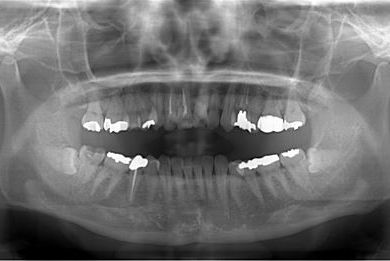

| 性別/年齢 | 女性 / 45歳 | ||||||||||||||||||||||||||||||||

| 主訴 | 右下奥虫歯による冠はずれと、前歯他冠治療済の他の虫歯の有無の確認。 | ||||||||||||||||||||||||||||||||

| 治療方針 | セラミック治療にて、審美的回復を行う。 | ||||||||||||||||||||||||||||||||

| 治療内容 | CAD/CAMオールセラミッククラウン3本(オールセラミック用土台3本)、ハイブリッドセラミックインレー2本 | ||||||||||||||||||||||||||||||||